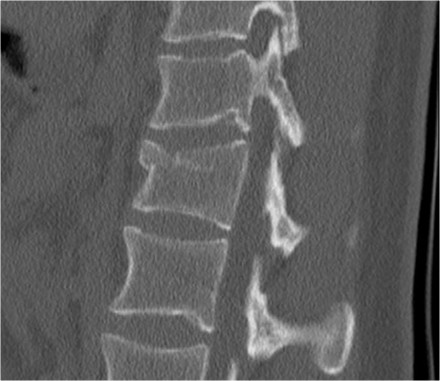

Burst fracture

This is the severe variant of a compression fracture with higher risk of neurologic deficits.

A burst fracture gets 2 points for morphology in the TLICS.

Sagittal fracture of vertebral body and posterior element

A sagittal fracture of the vertebral body and a sagittal posterior element fracture is seen in respectively 90% and 85% of cases of burst fracture cases.

Here are four examples.

In the Denis classification this would be a three column fracture -anterior/middle/posterior - indicating a very unstable fracture.

In the TLICS classification however this is a burst fracture, i.e. 2 points for morphology.

The treatment will depend on the PLC integrity and the neurological status.